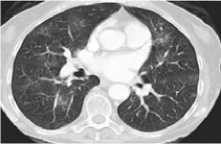

Примеры наиболее частых пульмонитов представлены на рисунке 1.

Пульмонит с множественными рассеянными уплотнениями легочной ткани по типу матового стекла

Рисунок 1. Виды Л-ИЗЛ